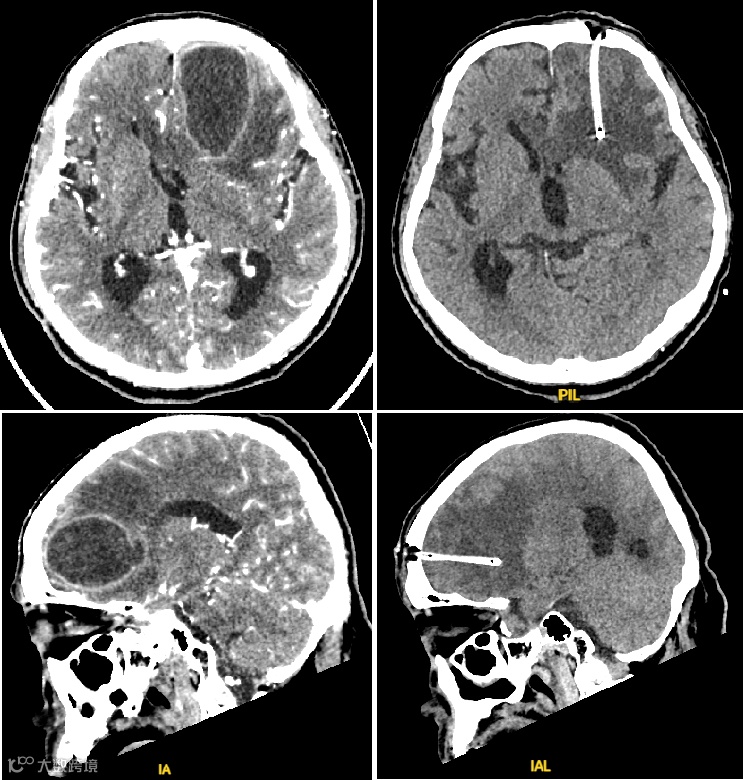

然而,手术成功的关键在于穿刺路径的精准无误,以避免对周围正常脑组织及功能区的损伤。传统手术多依赖术前的CT或MRI影像进行规划,无法实现真正的实时引导。

手术过程中,术者在常规使用术中导航系统的同时,将鲲为超声的低频经颅探头置于手术对侧。

整个操作过程流畅、直观,超声监测结果与术中导航系统显示的位置高度吻合,展示了该技术的精准性。

术后患者恢复良好,未出现任何神经功能损伤等并发症